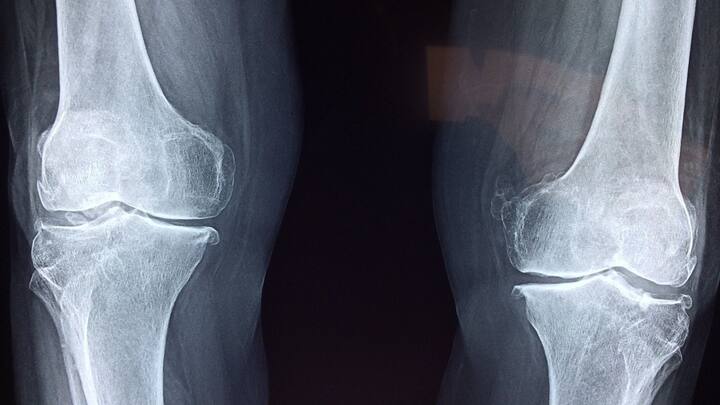

Knee Pain Home Remedies: হাঁটুর ব্যথায় মুশকিল আসান ঘরোয়া টোটকা

আজকাল ঘরে ঘরে রয়েছে হাঁটুব্যথার সমস্যা। অনেক পরিবারেই বয়স্ক সদস্যরা হাঁটুর ব্যথায় ভুগে থাকেন। প্রৌঢ়ত্বে পৌঁছলেই জবাব দিতে থাকে হাঁটু।

কখনও মাটিতে বসতে সমস্যা হয়। কখনও কষ্ট হয় সামান্য পথ হাঁটতে। অনেকের হাঁটু ফুলে যায়, অনেকের হাঁটু ভাঁজ করতেও সমস্যা হয়।